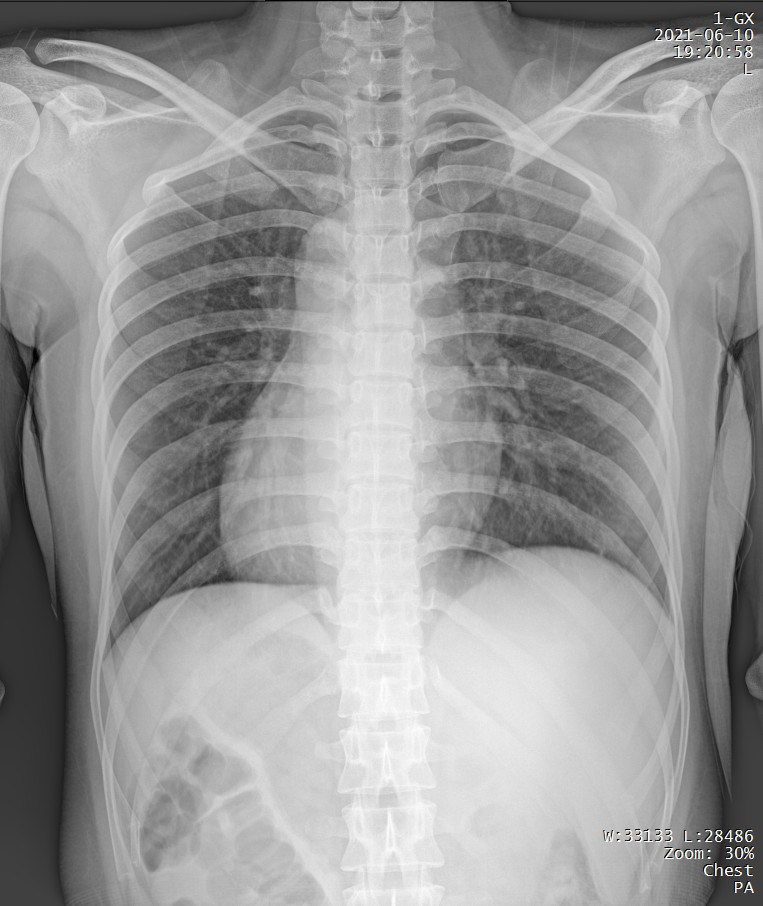

65kW大功率球管

肥胖患者、組織較厚部位清晰顯示

PLX5500輸出的射線能夠滿足各體型患者的拍攝需求,即便是體重達(dá)上百公斤的患者,也能夠獲得清晰的圖像。

短時曝光 定格心肺運動瞬間的影像

PLX5500能夠在短時曝光內(nèi)輸出足量的X射線,獲取清晰圖像。特別適用于拍攝肺炎、塵肺病、肺結(jié)核等難以憋氣的患者,避免因患者呼吸而產(chǎn)生運動偽影,便于醫(yī)生準(zhǔn)確診斷。

支持高千伏攝影 肺部紋理更有層次

PLX5500能夠輸出高能量X射線,與骨骼相重疊的軟組織或骨骼本身的細(xì)小結(jié)構(gòu)及含氣的管腔等,均可清晰顯示。